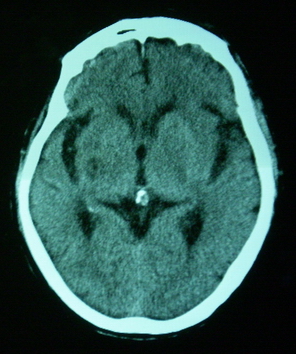

男,70岁,左侧肢体活动障碍口角向右侧歪斜2天,有高bp病史

pe:神情,能与之正常交流,吐字不清,180/90mmhg,双瞳孔无异常,左侧肢体肌力1级 b(+)

图中有个同心圆壮低密度影是ct伪影,见笑了。

1、右侧基底区及外囊区腔隙性脑梗塞。2、脑萎缩。

右基底节内囊前支区腔隙性脑梗塞,脑萎缩

支持右侧基底节区脑梗塞。

右侧基底区及外囊区腔隙性脑梗塞

右基底节区脑强隙 右基底节区低密度影密度太低 边界清 不会是2天的梗赛灶

2天左右的腔隙性脑梗死ct多难以发现 何况你的机器又差 很难显示 即使显示密度应该略低影

边缘模糊

支持腔梗。左内囊后肢亦有病灶